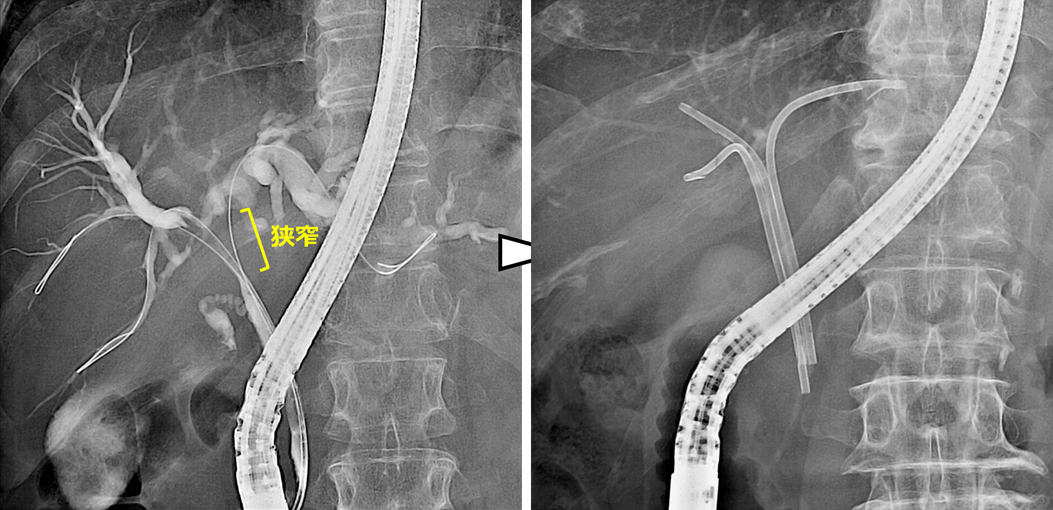

術後の胆管空腸吻合部の再発に対する胆道ドレナージ

肝門部領域胆管癌の術後に胆管空腸吻合部に再発を認めた症例です。

本症例はRoux-en-Y再建後であり、ダブルバルーン内視鏡を用いて胆管まで到達しました。胆管造影を行い、狭窄部を確認した後、前区域枝に2本、後区域枝に1本、合計3本のステントを留置しました。

左上:Roux-en-Y再建後でした。ダブルバルーン内視鏡を用いました。

右上:到達後、胆管造影を行い、狭窄部の確認をしました。

左下・右下:前区域枝に2本・後区域枝に1本のステントを留置しました。